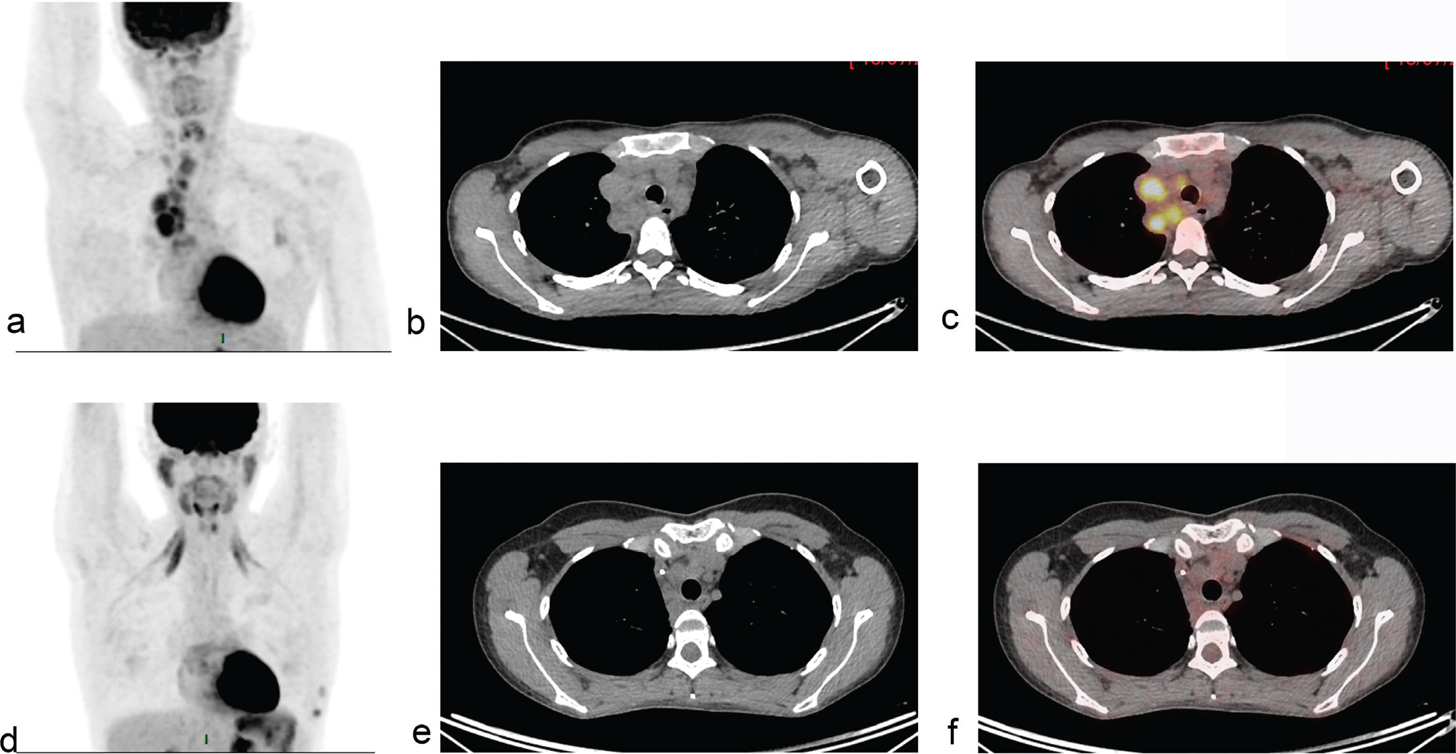

With the introduction of more novel therapies for HL, including immunotherapy with PD1 inhibitors, there was a need for response criteria that provided guidance on the interpretation of transient tumor flare phenomenon or pseudo-progressions that can occur in response to increased immunologic activity in tumors. Therefore, The Lymphoma Response to Immunomodulatory Therapy Criteria (LYRIC) was developed. This set of response criteria include the category indeterminate response to account for situations where individual tumor lesions increase in size or activity in the absence of clinical deterioration (41). At first glance these criteria could look like oxymora but how to define a response as indeterminate? The answer is that these cases need to be monitored closely with additional imaging or biopsy to distinguish pseudo progression from true progressions (Figure 4). Immunotherapies can lead to variable, transient immunologic flares that are shown as increased FDG-uptake and can resemble disease progressions (Figure 4).

Fig 4

Figure 4. 57-year-old woman with history of 2 HL relapses, the last one treated by Nivolumab. One year after starting nivolumab (PD1 immune check point inhibitor), she developed enlarged mediastinal and abdominal lymph nodes, diffuse pulmonary lesions (SUVmax=27.4) and a hepatic lesion, all with intense FDG uptake A, Biopsies revealed aseptic granuloma including well-formed giant cells consistent with sarcoid-like reaction. PET/CT after corticosteroids (b) showed improvement with a complete metabolic response of all lesions.